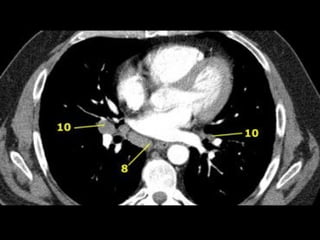

10. Hilar LNs

7. Subcarinal LNs

8. Paraesophageal LNs